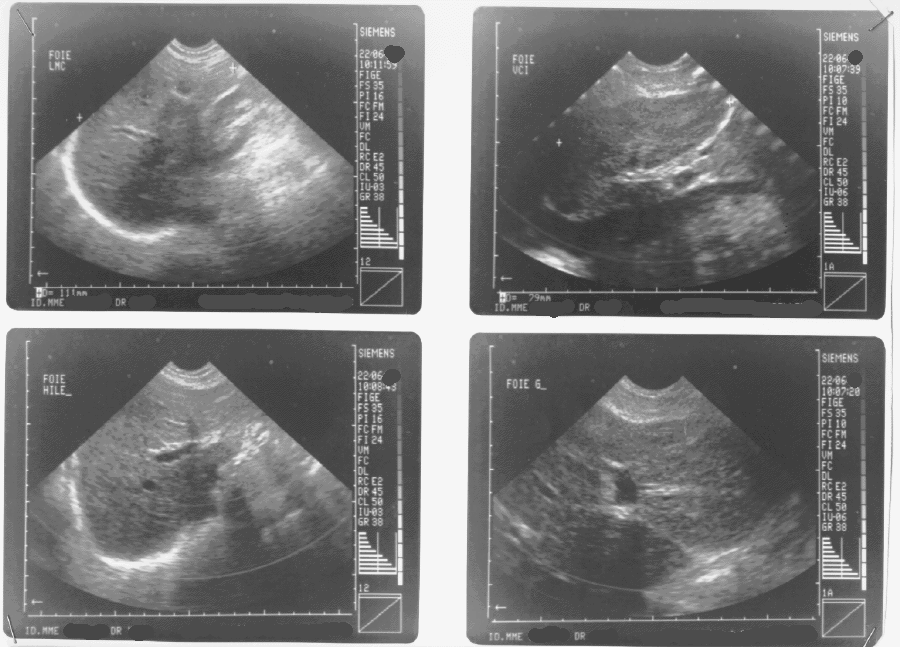

L'échographie est une technique d'imagerie médicale encore récente puisqu'elle est apparue il y a une vingtaine d'années. Elle tient une place importante dans le cadre d'un diagnostic.

2) Utilité L'échographie permet d'explorer toutes sortes d'organes (thyroïde, sein, muscle, foie, pancréas, rein, vessie mais aussi le fœtus).Couplée au technique Doppler, il est possible d'étudier les flux sanguins dans les artères et les veines, dans les organes ou dans les tumeurs.

D'un point de vue théorique, elle utilise un faisceau d'ondes ultrasonores, d'une fréquence adaptée (2.5 à 10 Mhz), qui sera plus ou moins réfléchi selon les structures organiques rencontrées. Sur le plan pratique, on promène une sonde sur la région à examiner après avoir appliqué sur la peau un gel qui permet de supprimer la présence d'air entre la sonde et la peau. L'examen dure 15 à 30 mn.

images